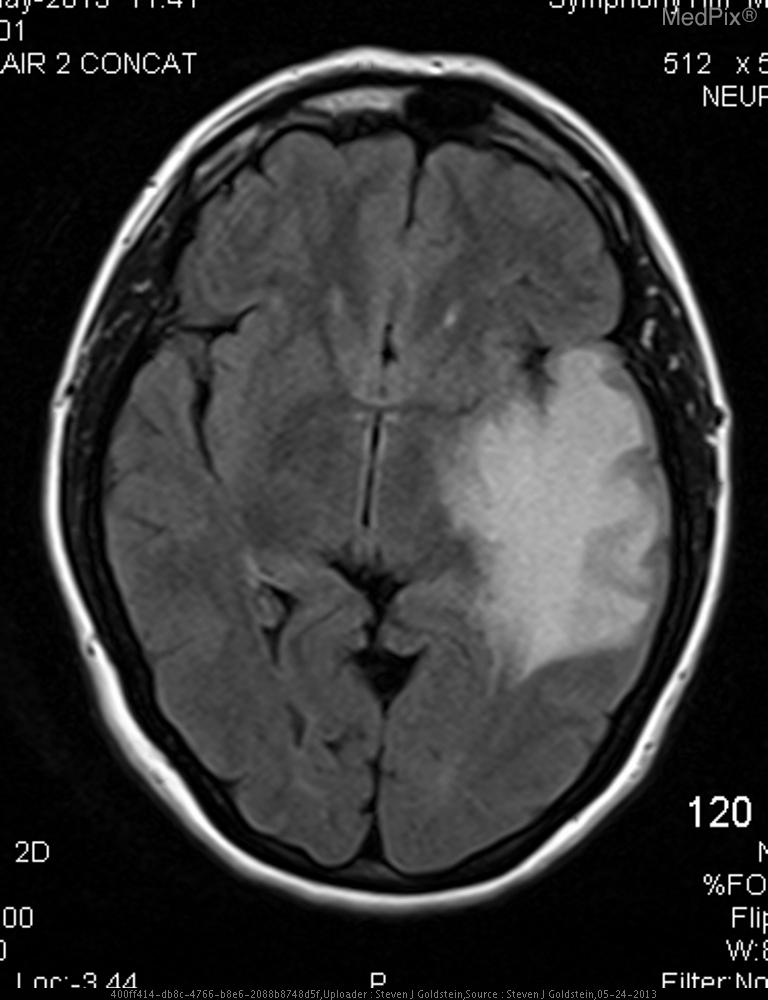

- A well-defined, extra-axial, dural-based mass is visible over the image-right (patient-left) frontoparietal convexity region.

- The lesion shows heterogeneously hyperintense signal intensity on this FLAIR MRI sequence.

- There is adjacent cortical sulcal effacement and underlying vasogenic edema extending into the adjacent white matter.

- Associated mild local mass effect with rightward (image-left, patient-right) midline shift is evident.

- The lesion margin appears broad-based against the inner table of the skull, with subtle dural thickening (“dural tail” sign possible).

- No hemorrhagic or cystic necrosis component clearly noted on this single sequence.

- Ventricles appear compressed on the image-right (patient-left) side due to mass effect.

- Cortical gray–white differentiation otherwise preserved outside the area of edema.

Extra-axial dural-based mass consistent with meningioma. The smooth, broad-based extra-axial location, dural attachment, and presence of vasogenic edema with mass effect are characteristic features of a meningioma. The rounded contour and preservation of cortical gray–white matter interface favor a meningioma over an intra-axial glioma. Context consistency: Consistent. The provided context indicates a 38-year-old female with “meningioma,” and imaging features align with this. Confidence: 90%.